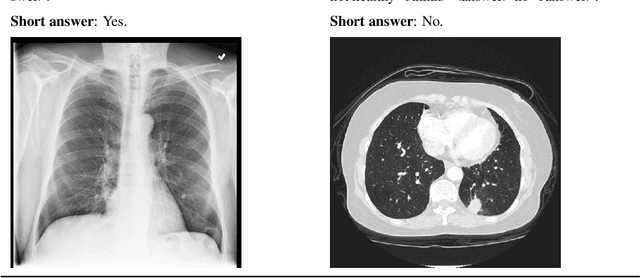

Abstract:Faithful reasoning in medical vision-language models (VLMs) requires not only accurate predictions but also transparent alignment between textual rationales and visual evidence. While Chain-of-Thought (CoT) prompting has shown promise in medical visual question answering (VQA), no large-scale expert-level dataset has captured stepwise reasoning with precise visual grounding. We introduce S-Chain, the first large-scale dataset of 12,000 expert-annotated medical images with bounding boxes and structured visual CoT (SV-CoT), explicitly linking visual regions to reasoning steps. The dataset further supports 16 languages, totaling over 700k VQA pairs for broad multilingual applicability. Using S-Chain, we benchmark state-of-the-art medical VLMs (ExGra-Med, LLaVA-Med) and general-purpose VLMs (Qwen2.5-VL, InternVL2.5), showing that SV-CoT supervision significantly improves interpretability, grounding fidelity, and robustness. Beyond benchmarking, we study its synergy with retrieval-augmented generation, revealing how domain knowledge and visual grounding interact during autoregressive reasoning. Finally, we propose a new mechanism that strengthens the alignment between visual evidence and reasoning, improving both reliability and efficiency. S-Chain establishes a new benchmark for grounded medical reasoning and paves the way toward more trustworthy and explainable medical VLMs.

Abstract:The growing integration of vision-language models (VLMs) in medical applications offers promising support for diagnostic reasoning. However, current medical VLMs often face limitations in generalization, transparency, and computational efficiency-barriers that hinder deployment in real-world, resource-constrained settings. To address these challenges, we propose a Reasoning-Aware Reinforcement Learning framework, \textbf{RARL}, that enhances the reasoning capabilities of medical VLMs while remaining efficient and adaptable to low-resource environments. Our approach fine-tunes a lightweight base model, Qwen2-VL-2B-Instruct, using Low-Rank Adaptation and custom reward functions that jointly consider diagnostic accuracy and reasoning quality. Training is performed on a single NVIDIA A100-PCIE-40GB GPU, demonstrating the feasibility of deploying such models in constrained environments. We evaluate the model using an LLM-as-judge framework that scores both correctness and explanation quality. Experimental results show that RARL significantly improves VLM performance in medical image analysis and clinical reasoning, outperforming supervised fine-tuning on reasoning-focused tasks by approximately 7.78%, while requiring fewer computational resources. Additionally, we demonstrate the generalization capabilities of our approach on unseen datasets, achieving around 27% improved performance compared to supervised fine-tuning and about 4% over traditional RL fine-tuning. Our experiments also illustrate that diversity prompting during training and reasoning prompting during inference are crucial for enhancing VLM performance. Our findings highlight the potential of reasoning-guided learning and reasoning prompting to steer medical VLMs toward more transparent, accurate, and resource-efficient clinical decision-making. Code and data are publicly available.

Abstract:Medical Visual Language Models have shown great potential in various healthcare applications, including medical image captioning and diagnostic assistance. However, most existing models rely on text-based instructions, limiting their usability in real-world clinical environments especially in scenarios such as surgery, text-based interaction is often impractical for physicians. In addition, current medical image analysis models typically lack comprehensive reasoning behind their predictions, which reduces their reliability for clinical decision-making. Given that medical diagnosis errors can have life-changing consequences, there is a critical need for interpretable and rational medical assistance. To address these challenges, we introduce an end-to-end speech-driven medical VLM, SilVar-Med, a multimodal medical image assistant that integrates speech interaction with VLMs, pioneering the task of voice-based communication for medical image analysis. In addition, we focus on the interpretation of the reasoning behind each prediction of medical abnormalities with a proposed reasoning dataset. Through extensive experiments, we demonstrate a proof-of-concept study for reasoning-driven medical image interpretation with end-to-end speech interaction. We believe this work will advance the field of medical AI by fostering more transparent, interactive, and clinically viable diagnostic support systems. Our code and dataset are publicly available at SiVar-Med.